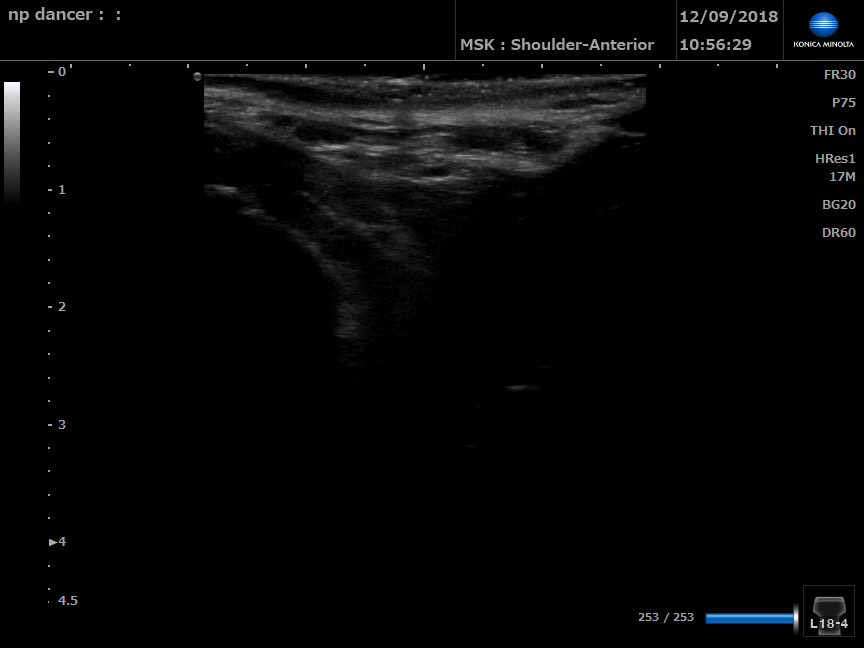

Dancer with pelvic floor dysfunction

B Mode ultrasound of right perineal body